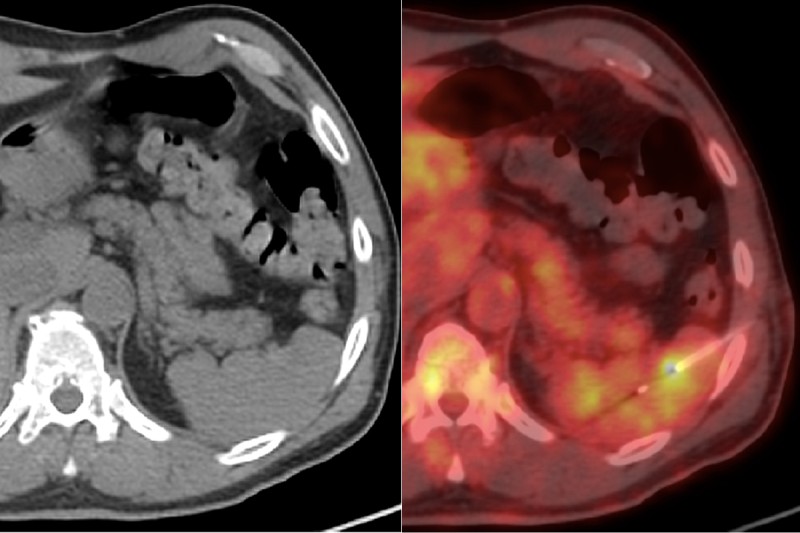

CT and PET/CT images of needle biopsy

These images show a needle biopsy of a spleen in a patient with lymphoma. In the regular CT image (left), the tumor and needle are difficult to see. In the PET/CT image, both are visible, demonstrating the value of this technology.